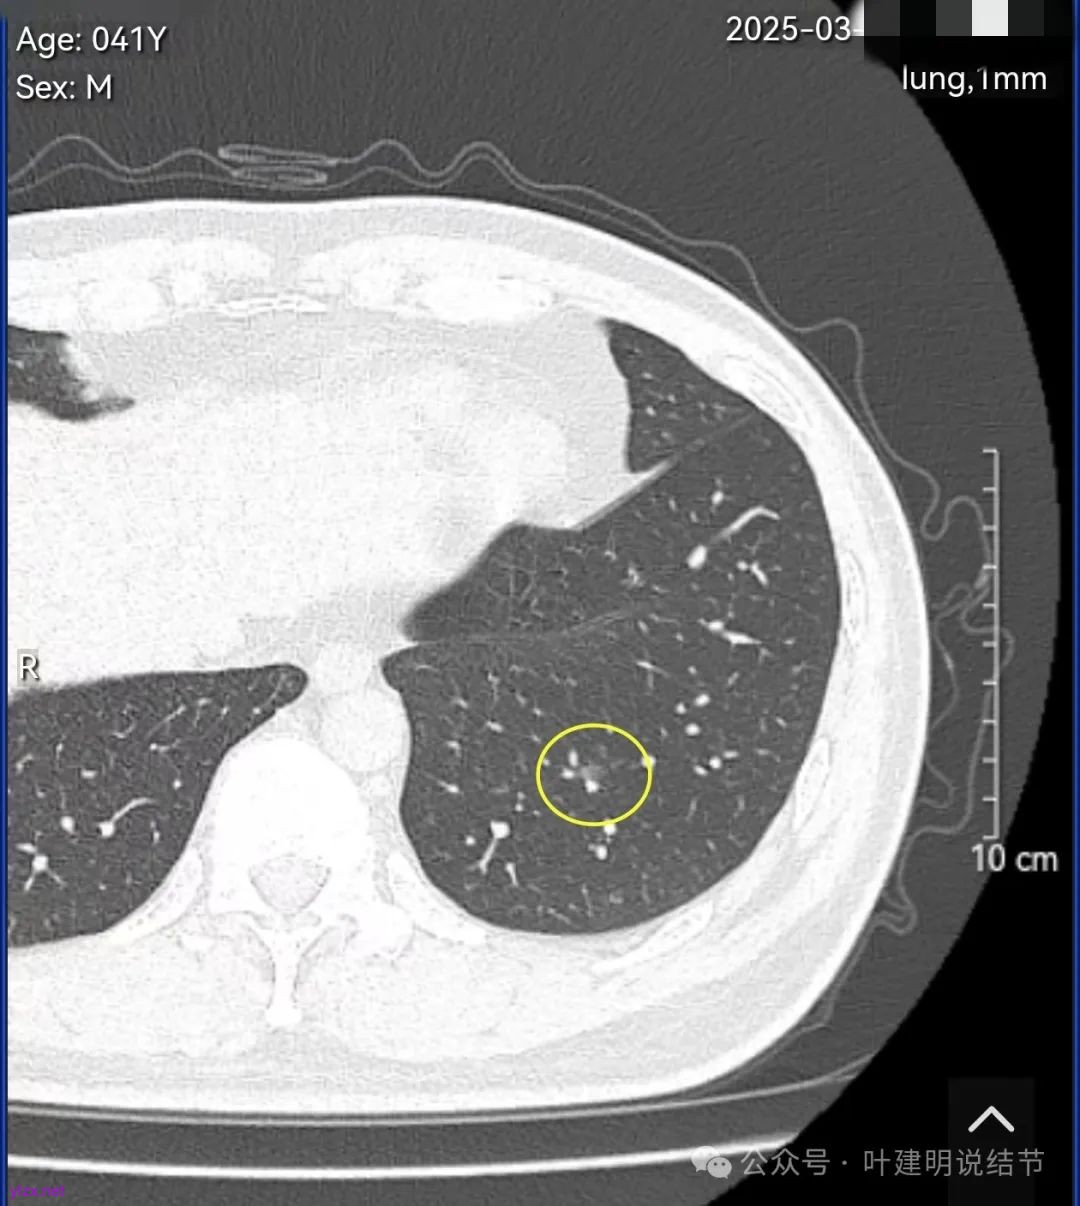

结友男性,41岁,具体病史记不得了,下面是请他重新发我的术前CT报告中截图的影像。

左下叶基底段淡磨玻璃结节,轮廓与边界清楚,考虑肺泡上皮增生可能性大。

左下叶胸膜下很淡但边缘不光滑的磨玻璃结节,考虑肺泡上皮增生可能性大,或者肺泡间隔增宽。